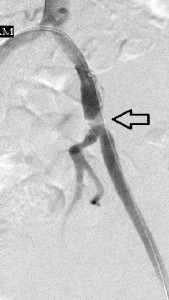

I present here a young woman whose primary care physician referred to me because of acute pain in her left great toe that was associated with discoloration. Her left common femoral pulse was diminished on examination and its waveform abnormal on arterial Doppler sonography. The image to the far left of the reader shows a focal filling defect of the distal left common iliac artery with sharp margins between its upper and distal surfaces and the vessel lumen, a calcified plaque from which a small embolus may have arisen. The rest of her angiography was normal. The middle image shows the deployment of a short balloon-expandable stent across the filling defect, while the image to the reader’s right is the post-intervention study that shows restoration of normal blood flow through the left iliac channel. Her symptoms resolved and she returned to her primary care provider on aspirin, Plavix, and advice to quite smoking, while pursuing hypercoagulability workup with him.